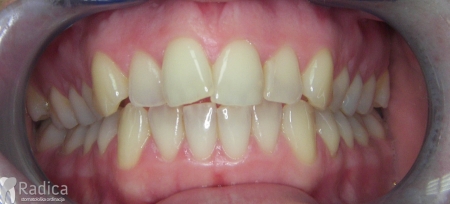

Slučaj 2: ispravljanje kompresije Invisalign full terapijom- u ovom slučaju je izvađen jedan donji sjekutić